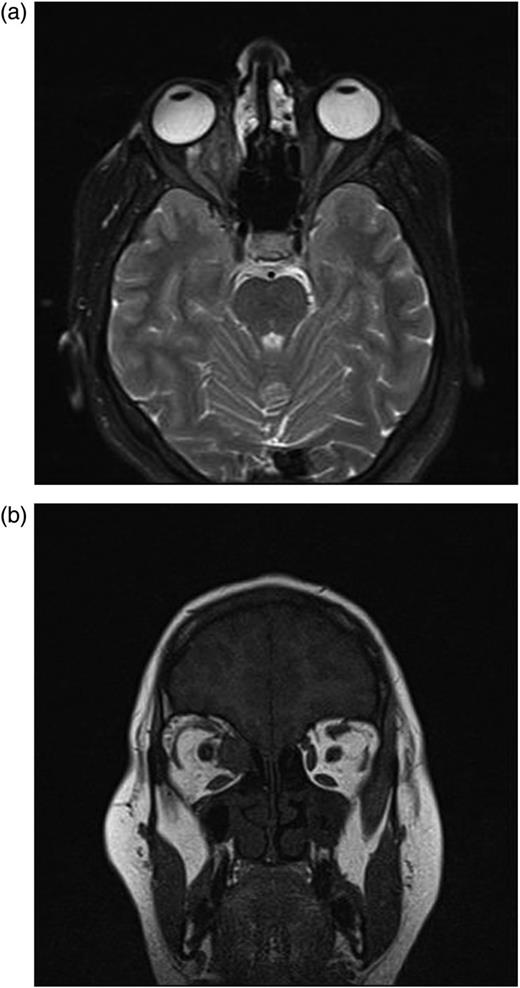

A complete blood cell count and serum laboratory values were normal without mild eosinophilia. Axial-coronal orbital magnetic resonance imaging (MRI) revealed a well-defined homogenous unilocular lesion in intraconal region of the right orbita which was hypointense on T1-weighted images and hyperintense on T2-weighted images after an intravenous injection of gadolinium-ethoxybenzyl-diethylenetriamine pentaacetic acid (Fig. 2a and b). The lesion was adjacent to optic nerve and medial rectus muscle and exerting pressure on the optic nerve and displacing optic nerve laterally. Approximate dimension of the lesion was 2 cm × 2 cm × 2 cm (Fig. 2a and b). Because it was difficult to distinguish hydatid cyst from other mass lesions of the orbita via MR, other mass lesions like neurocysticercosis, dermoid, lipodermoid, mucocele, encephalocele, inclusion cyst, teratoma, hematocele, schwannoma and paraganglioma were considered in the differential diagnosis of hydatid cyst.

(a and b) Axial-coronal orbital magnetic resonance imaging show the homogenous unilocular lesion that is adjacent to optic nerve and medial rectus muscle in the intraconal space and displacing optic nerve laterally.